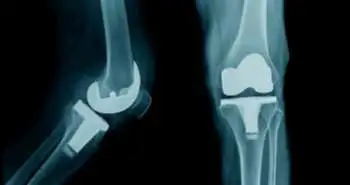

Elderly population across the world tends to suffer from osteoarthritis of the knees which could seriously affect their health and quality of life. Total knee arthroplasty (TKA) is a surgical procedure used to reduce pain and improve quality of life and function in patients when the disease progresses and becomes severe. Simultaneous bilateral TKA is an effective and safe approach for selected patients. The possibility of having different satisfaction levels between the first and second knee in the early stage after Shuai Huang et al. assessed simultaneous bilateral TKA.

A total of 46 patients were retrospectively assessed in the Department of Joint Surgery, The First Affiliated Hospital of Sun Yat-sen University, China between March 2013 and March 2015. Typically, the surgeon executed first-side TKA (right knee), followed by TKA on the left knee. Tranexamic acid (TXA) (10 mg/kg) was administered intravenously, and the tourniquet was released after wound closure. The objective parameters comprising drainage volume and swelling evaluated by the circumference of the 10 cm above the patella; preoperative KSS (Knee Society Score), ROM (Risk of Mortality), and pain visual analog scale (VAS) and the preoperative and postoperative (1st, 3rd, and 7th days) subjective parameters comprising pain, patient satisfaction and VAS of the first and second surgeries for each knee were investigated.

On comparison of simultaneous bilateral TKA, the first-side TKA (right knee) showed lower mean drainage volume (p < 0.05). However, the swelling of the knee was higher on the 1st, 3rd, and 7th postoperative days (p < 0.05). Also, the first-side TKA scored lower in satisfaction VAS, but higher in pain VAS at the 1st, 3rd, and 7th postoperative days.  As per the patient satisfaction scores, 2 (4.4%) of the 46 patients rated first-side TKA higher than second-side TKA, 34 (73.9%) of the 46 patients rated second-side TKA higher than first-side TKA, and 10 (21.7%) of the 46 patients rated their satisfaction as the same for both knees.

Overall, there was better patient satisfaction with the second knee in the early stage following simultaneous bilateral TKA. This may supplement some considerations for surgeons opting for simultaneous bilateral TKA for patients suffering from osteoarthritis in both knees.